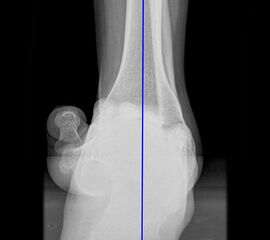

Sprunggelenk ap mit Belastung

Positionierung:

• Der Patient steht, beide Beine sind geleichmäßig belastet.

• Die Fußachse verläuft parallel zum Zentralstrahl.

• Der Zentralstrahl ist zentral auf den Gelenkspalt des oberen Sprunggelenks ausgerichtet.

• Die Röntgenkassette liegt dem Fuß dorsal an.

Kennzeichen des Röntgenbildes:

• Darstellung des Talusdoms mit lateraler Überlagerung durch die Fibula.

• Das Sprunggelenk befindet sich dabei in 90° Stellung.

• Der Weichteilmantel ist erkennbar.

Besondere Bemerkungen zum Beispielbild:

• Subfibulare Verkalkung nach mehreren Distorsionen.

• Gut erkennbar ist die für eine ap Aufnahme typische Überlappung von Fibula und lateralem Talus.

Zur Vollansicht und zum Lesen der Bildbeschreibung bitte die Bilder anklicken.